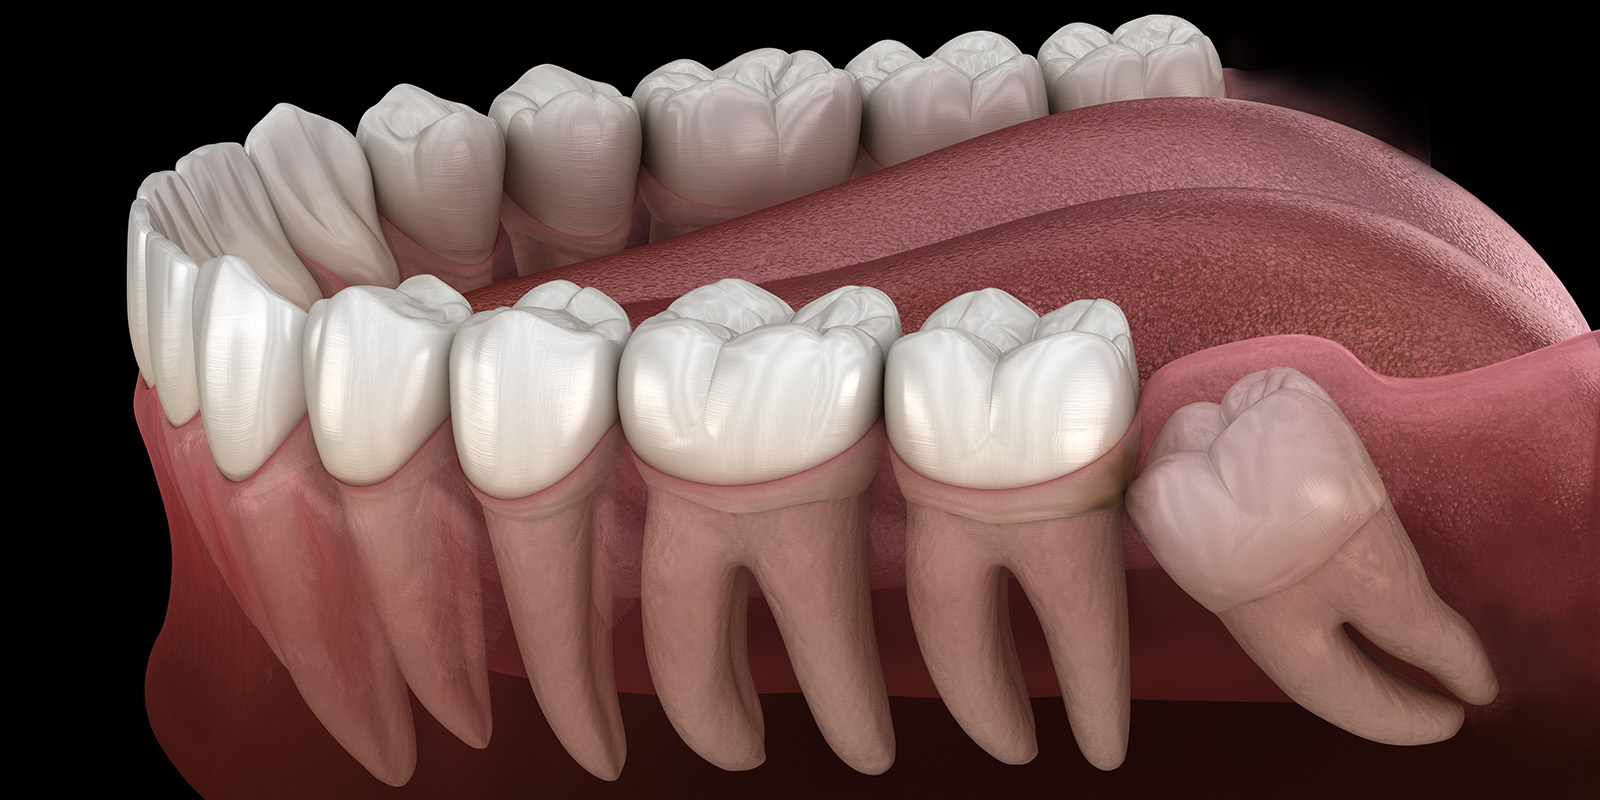

親知らずが生えそろっている下の歯のイラスト

親知らずは、第三大臼歯と呼ばれる8番目の歯になります。顎の大きさ、他の歯と同様に生えたり、横に生えたり、完全に埋まっていたり、元々なかったり、人によって全く違ってきます。